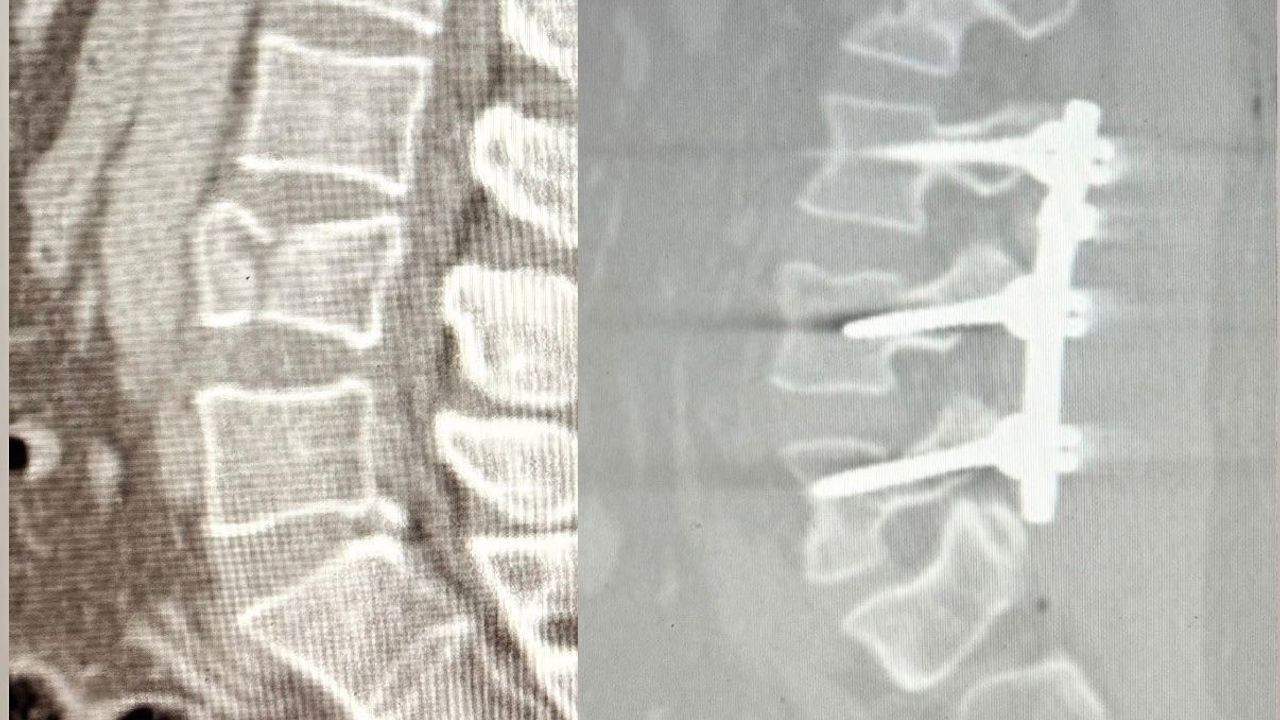

Ameliyat sırasında bel bölgesindeki omurların sabitlenmesini sağlayan lomber stabilizasyon tekniği kullanıldı. Hastane tarihinde ilk kez gerçekleştirilen bu operasyon sonrası hasta sağlıklı şekilde yürümeye başladı.